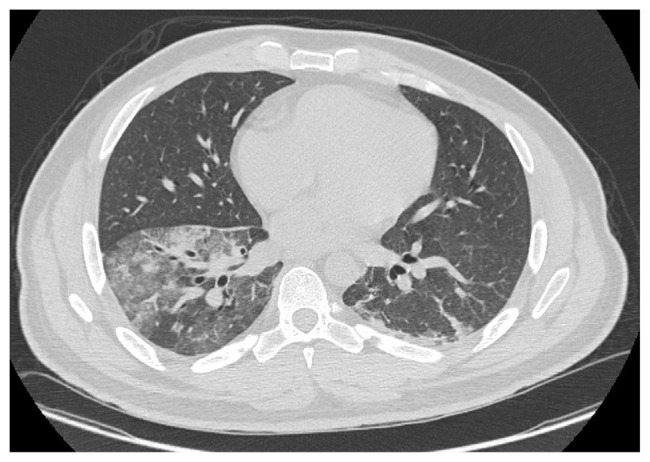

Carbon black is the general term for a powdery commercial form of carbon. It can cause adverse health effects after inhalation, ingestion, or dermal contact. Exposure to carbon black particles can have adverse effects on the respiratory system; this exposure usually occurs when people inhale contaminated air in the workplace. Here we report a patient with massive carbon black exposure at work who continues to have productive cough with black material in sputum for over a year after this one-time exposure. This patient worked as a repair man and welder at a carbon black manufacturing facility. He had an intense exposure to carbon black for 4-10 min when equipment in the plant malfunctioned. He developed immediate respiratory symptoms, and these have persisted for at least 1.5 years post exposure with a chronic productive cough with black particles. Cytological analysis of his sputum revealed carbon laden macrophages. A high-resolution computed tomography scan documented patchy alveolar infiltrates at the lung bases with septal thickening. His symptoms have partially improved with empiric treatment with a long-acting beta agonist and inhaled corticosteroids. This case demonstrates that a single one-time exposure to a dense fog of carbon black can result in particle deposition in the lung that persists for prolonged periods of time.

炭黑是一种粉状商业形式的碳的总称。吸入、摄入或皮肤接触后可对健康造成不良影响。接触炭黑颗粒会对呼吸系统产生不良影响;这种接触通常发生在人们在工作场所吸入被污染的空气时。在这里,我们报告了一个在工作中大量接触炭黑的病人,在这一次接触后,他的痰中有黑色物质持续咳了一年多。该患者在一家炭黑制造工厂担任修理工和焊工。当工厂的设备发生故障时,他在炭黑中暴露了4-10分钟。他立即出现呼吸道症状,这些症状在接触后持续至少1.5年,伴有带黑色颗粒的慢性生产性咳嗽。痰液细胞学分析显示含碳巨噬细胞。高分辨率计算机断层扫描显示肺底斑片状肺泡浸润伴间隔增厚。经经验性治疗,使用长效受体激动剂和吸入皮质类固醇,他的症状得到部分改善。本病例表明,一次暴露于炭黑浓雾中可导致肺部颗粒沉积,并持续很长一段时间。